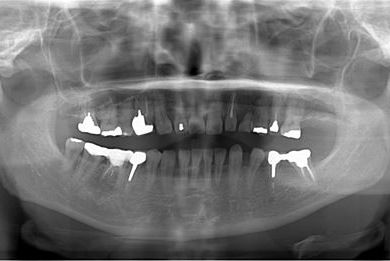

インプラントの症例写真 IMPLANT

インプラント治療

| 主訴 | 乳歯がぐらついている。 | ||||||||||||||||||||||||||||||||

| 治療方針 | インプラント治療にて、機能的・審美的回復を行う。 | ||||||||||||||||||||||||||||||||

| 治療内容 | インプラント1本、メタルボンドセラミッククラウン1本 | ||||||||||||||||||||||||||||||||

| 総治療費 | 377,055円 | ||||||||||||||||||||||||||||||||

| 治療期間 | 4ヶ月 |